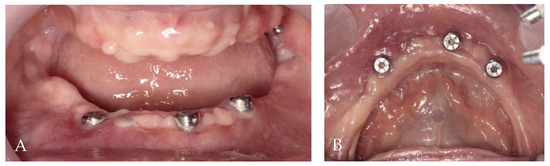

3.2. Surgery 1—Teeth Extraction and Periodontal Lesion Enucleation with Simultaneous Implantation

3.3. Surgery 2—Apically Positioned Partial-Thickness Flap (APPTF) in Combination with Free Gingival Grafts (FGGs)